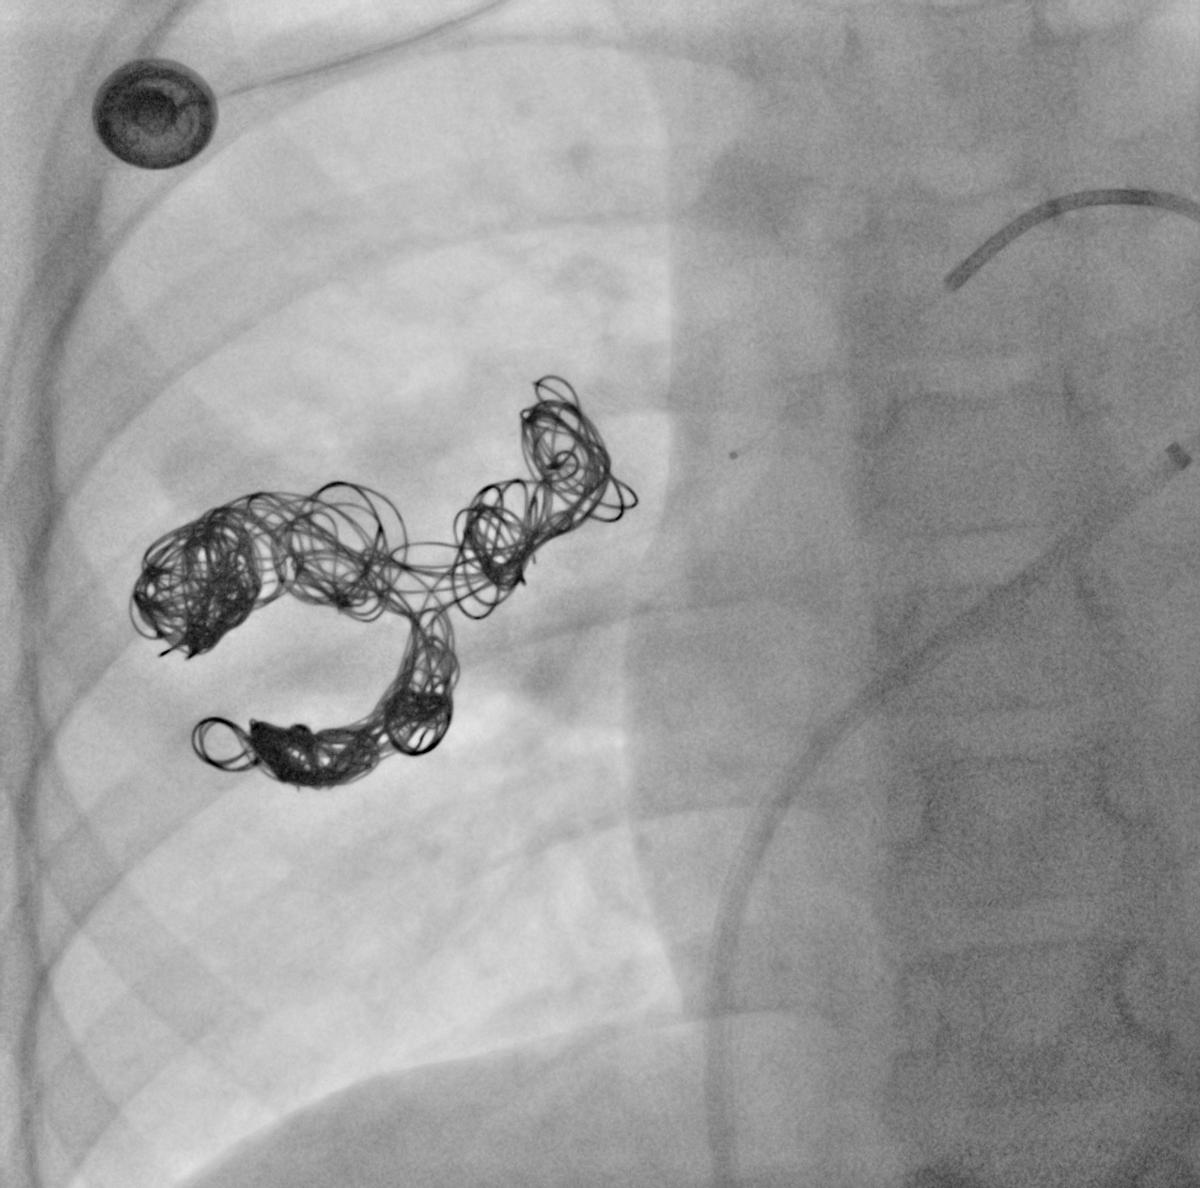

弹簧圈栓塞囊腔+供血动脉

小朋友经过介入栓塞治疗后症状明显好转,术后复查状态良好,希望小朋友早日康复!